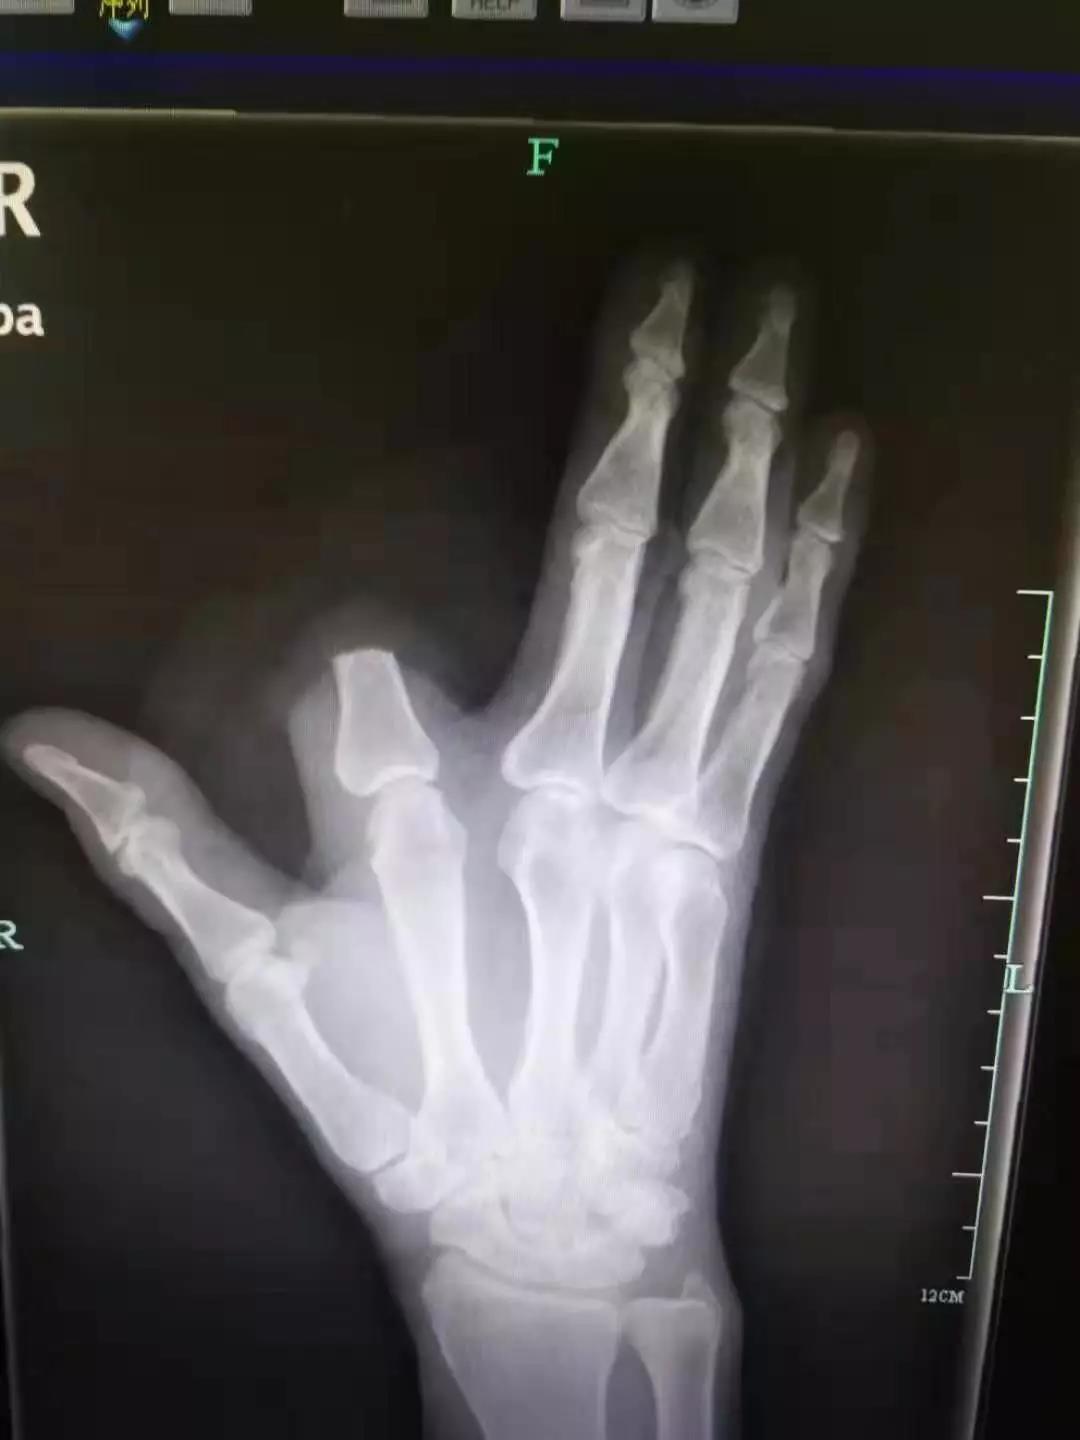

4小时前,他在山上干活时,食指被毒蛇咬了一口。“打开一看,我们发现患者的食指少了一大截。”袁丞达一问,张先生颤抖着回答,“砍了,保命要紧!”

原来,被咬后,张先生仔细一看,发现伤人的是条剧毒五步蛇,怕自己走动后毒性发作,一时恐惧紧张,就拿刀将自己的食指斩断了。

事后,他将断指就地丢弃,没有一并带到医院。检查结果出来,张先生的凝血功能正常,医生为他注射了抗蛇毒血清。本来,断指尚可以再植,如今,只能由骨科医生手术处理断指残端,张先生也将留下终身残疾。